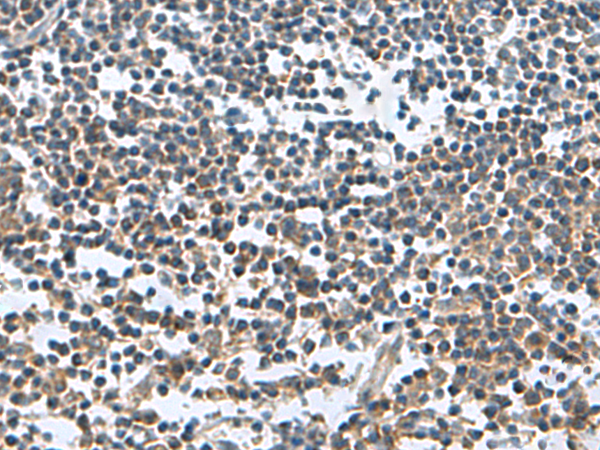

IHC positive control: |

Human tonsil |

IHC Recommend dilution: |

150-300 |